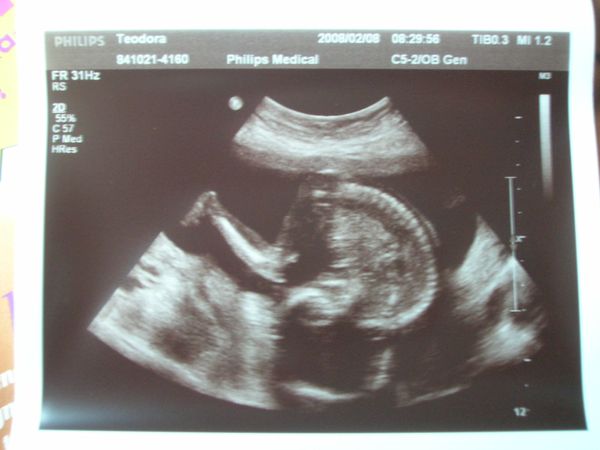

és ismét hason 2008.02.08 10:09